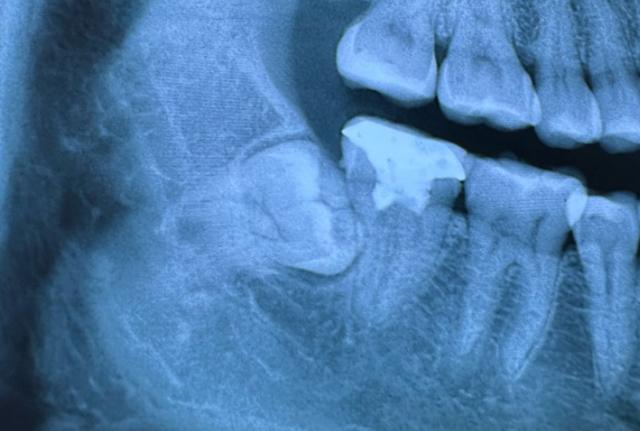

术中最需警惕的就是下牙槽神经损伤,我们下颌后牙区域分布着密集的神经,尤其是下牙槽神经,直接支配着嘴唇、下巴的感觉。

如果术前没有通过CBCT精准评估神经位置,或者手术中操作出现轻微偏差,就可能损伤这条神经,导致嘴唇麻木、刺痛。

严重时这种不适甚至可能永久无法恢复。除了神经损伤外,手术过程中还可能出现哪些急性并发症,需要我们重点警惕?

手术中还可能发生异常出血、上颌窦黏膜穿通等情况,尤其是上颌后牙区,牙槽骨较薄,距离上颌窦较近,操作不当就可能穿破黏膜,引发上颌窦炎。